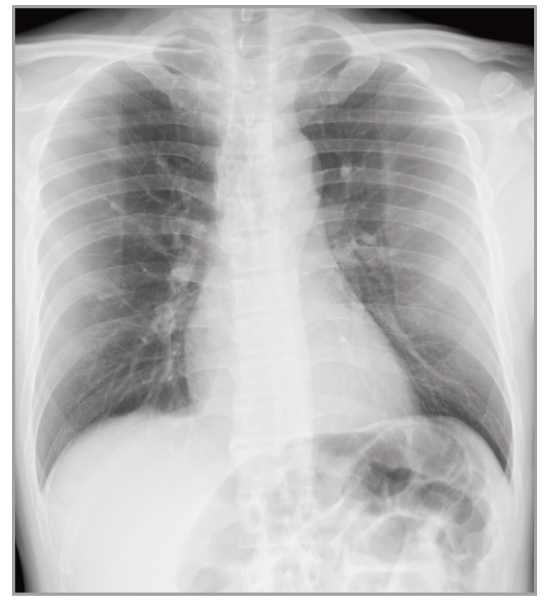

Virtual Grid​

No Grid

Virtual Grid

Real Grid